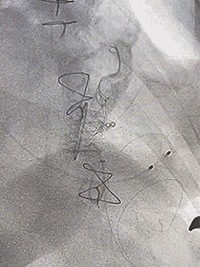

术中最佳投射角度:RAO 37° / CRA 20°

经心尖同轴性良好

DSA引导下定位心尖,心尖穿刺后置入泥鳅导丝及导管。利用导丝导管配合,穿过二尖瓣生物瓣。通过二尖瓣后置换加硬导丝。沿加硬导丝,置入J-Valve植入器。

术中,术者可以通过观察定位件跳动的形态判断瓣膜位置,同时可以清晰感觉到力的反馈。经过几次调试,定位件稳稳锚定原瓣架,可看到三个定位件随着心脏搏动而自然摆动。确定好位置后释放瓣膜,锁丝脱钩,瓣膜与植入器完全分离。观察瓣周漏与瓣膜形态,经食管超声心动图显示瓣膜位置合适,形态良好,无瓣周漏和反流。